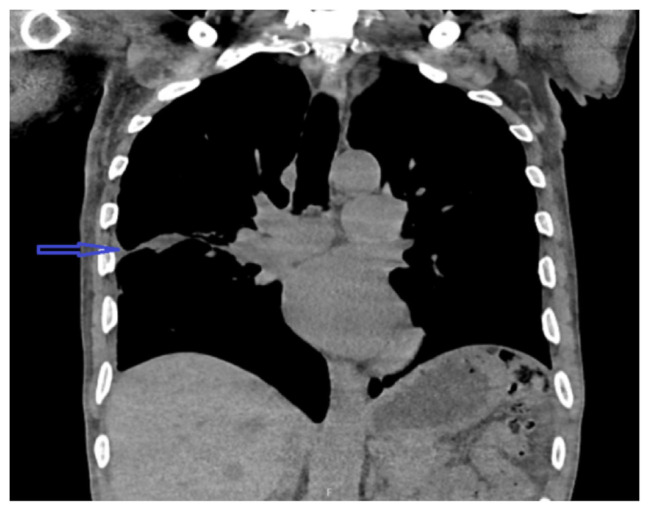

Streptococcus pyogenes is a rare cause of empyema, especially in immunocompetent individuals. The organism expresses various virulence factors leading to rapid progression of the disease. We report a case of rapidly progressing bilateral loculated empyema caused by streptococcus pyogenes in an immunocompetent host without additional risk factors.